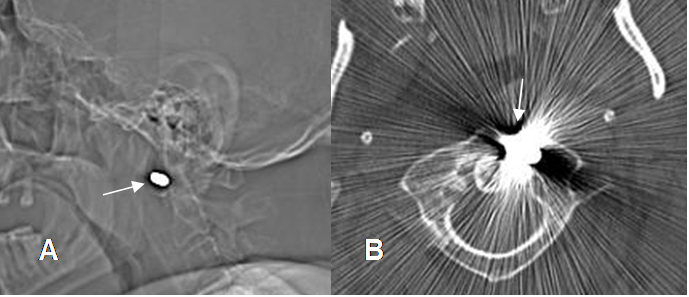

Fig 33. Cuerpo extraño. Paciente con antecedente de trauma abierto en la cara.

A: Rx AP. Imagen lineal y densa en la región malar izquierda.

B: Ecografía. Lesión ecogénica con hiper-refringencia posterior.

C: TAC axial y D: TAC reconstrucción en 3D. Imagen densa proyectada por debajo del hueso malar, que corresponde a cuerpo extraño. (Vidrio).